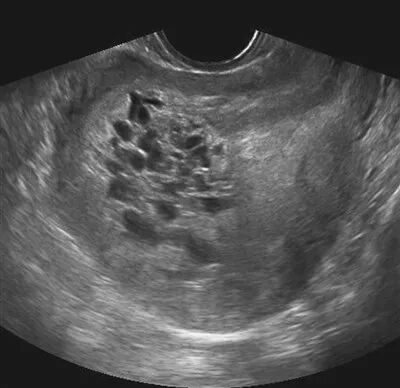

中午下班的丈夫见到依萍,吓坏了,立即将依萍送到医院,但是医院检查结果让依萍不敢相信……B超检查显示,依萍的宫腔内可见多个圆形、椭圆形不规则水泡状的东西,呈蜂窝状,就跟葡萄一样,根本没有胎儿、胎盘、羊水。

原来依萍怀的是葡萄胎,医生检查后发现,怀孕三个来月的肚子应该还不会隆起,可依萍的肚子却像怀孕五个月那么大,而据医生介绍,葡萄胎就是妊娠后胎盘绒毛滋养细胞增生,间质高度水肿,形成大小不一的水泡,水泡间相连成串,形状就像葡萄一样。葡萄胎的病人的子宫会明显大于停经的月份。